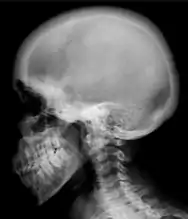

Renal osteodystrophy is usually diagnosed after treatment for end-stage kidney disease begins; however the CKD-MBD starts early in the course of CKD.[1][6] In advanced stages, blood tests will indicate decreased calcium and calcitriol (vitamin D) and increased phosphate, and parathyroid hormone levels. In earlier stages, serum calcium, phosphate levels are normal at the expense of high parathyroid hormone and fibroblast growth factor-23 levels. X-rays will also show bone features of renal osteodystrophy (subperiostic bone resorption, chondrocalcinosis at the knees and pubic symphysis, osteopenia and bone fractures) but may be difficult to differentiate from other conditions. Since the diagnosis of these bone abnormalities cannot be obtained correctly by current clinical, biochemical, and imaging methods (including measurement of bone-mineral density), bone biopsy has been, and still remains, the gold standard analysis for assessing the exact type of renal osteodystrophy.[6][16]

Ground glass density of the skull.[18]